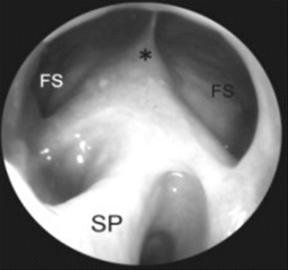

【引言】患者常感鼻咽干燥不适,有粘稠的痰液粘附,常有清嗓动作,并能感觉有涕液从上向下流到口咽部;咽后壁可见淋巴滤泡等。很多不明原因、不同部位的头痛、昏沉、低热、咽部异物感、嗅觉异常、口鼻异味,耳闷堵等症状。出现一些全身性的疾病症状,如风湿性关节炎、...